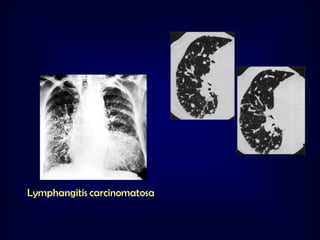

• 13.

Approach to DPLD DPLDof known Cause Idiopathic Interstitial Pneumonias Exposure Drugs Hypersensitivity Pneumonitis CVD Pneumoconiosis IPF Granulomatous Lung Diseases (Sarcoidosis) IIP other than IPF Desquamative Interstitial Pneumonia Others LAM Histiocytosis X Malignancy Respiratory BronchiolitisInterstitial Lung disease IPF: 47-64% NSIP: 14 to 36% Toxic Inhalation Radiation Acute Interstitial Pneumonia Cryptogenic Organizing Pneumonia RBILD/DIP: 1017% COP: 4-12% AIP: 2% LIP: 2% Lymphocytic Interstitial Pneumonia Non Specific Interstitial Pneumonia

Lymphangitis carinomatosa F 59Y,with radical mastectomy

Lymphangitic carcinomatosis. This 53-year-old man

presented with chronic obstructive pulmonary disease and

large-cell bronchogenic carcinoma of the right lung.

CT scan shows unilateral nodular thickening (arrows) and a

malignant right pleural effusion.